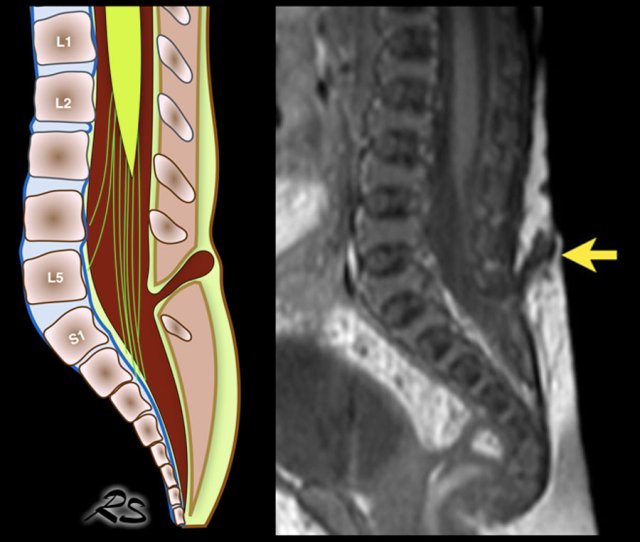

Diastematomyelia

Diastematomyelia, also named split cord malformation, is a longitudinal split of the spinal cord.

At the point of division, there may be an osseous, fibrous or cartilaginous dividing septum.

Diastematomyelia is commonly associated with a vertebral column abnormality and a tethered spinal cord.

The ultrasound diagnosis is usually straightforward.

Here images of a newborn, who had several antenatal anomalies.

There was a lateral rocker bottom feet deformity, lumbar kyphoscoliosis and swelling on the lower back.

The spinal US and MR show a longitudinal split of the spinal cord at the thoracolumbar level.

The bifid cord is asymmetric in volume.

Additional plain films of the lumbar spine and pelvis showed thoracic and lumbar hemivertebrae.

There was also a dislocated left hip.